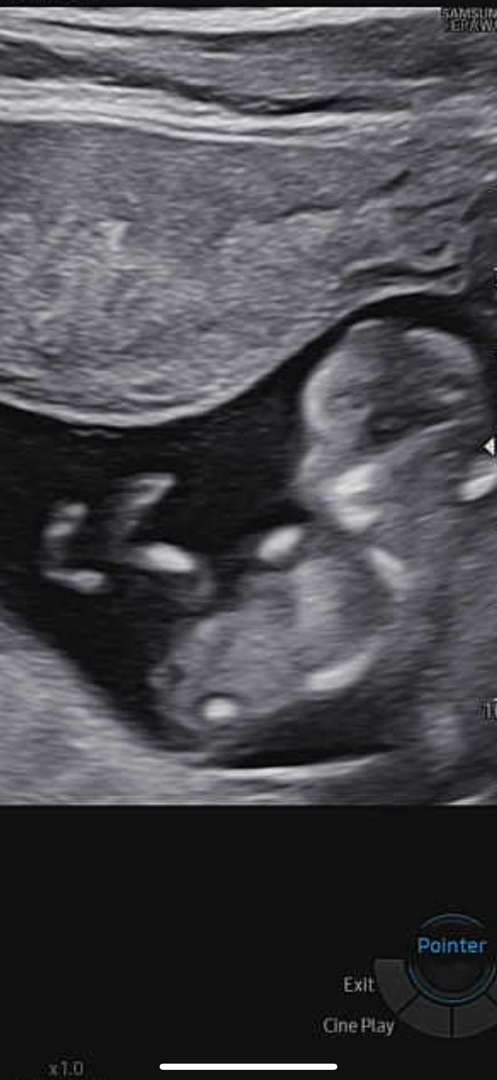

12주 각도법 볼줄아시는분 한번봐주세용

몰까요ㅠㅠ넘 애매하져ㅜㅜ